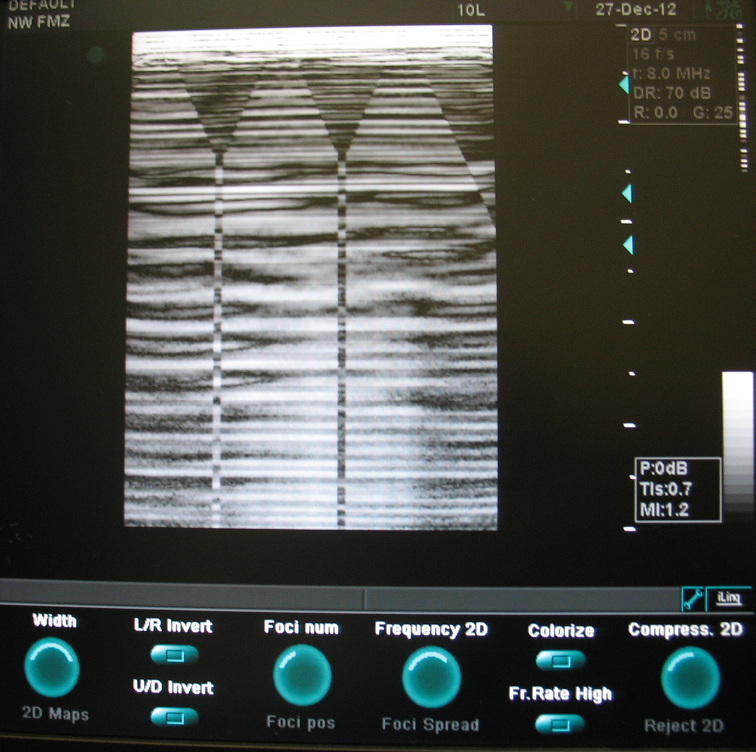

Аппарат очень болен. У него есть как минимум 3 неисправности:

1. После проверки Чек Диском, исправления ошибок и замены нечитаемых секторов, к последнему разделу Swap пропал доступ см. Рис. 1.

2. Тест платы FB, показал, что в одном из каналов завал, и предложил заменить одну из плат TP4 См. рис. 2. Поменял платы местами, результат тот же.

3. Тест платы BF, выдал ошибку цифровых тестов См. рис. 3.

4. В бычном режиме картинка см. рис. 4. Если немного согнуть плату BF, то на изображении пропадают треугольники см. рис. 5, 6. Одновременно при сгибании платы исчезает ошибка АЦП BF см. рис. 7, 8 в след. посте.

По началу аппарат иногда выдавал нормальную картинку, и цифровой тест Бимформера первый проходил всегда, второй иногда.

Может это было совпадение, но вроде всё так. Поэтому основной вопрос наверное - это из за чего бимформер может не проходить цифровые тесты, как с этим бороться и может ли это быть из за софта?

И ещё, как я понял все неисправности с завалами сигналов не так сильно влияют на картинку.